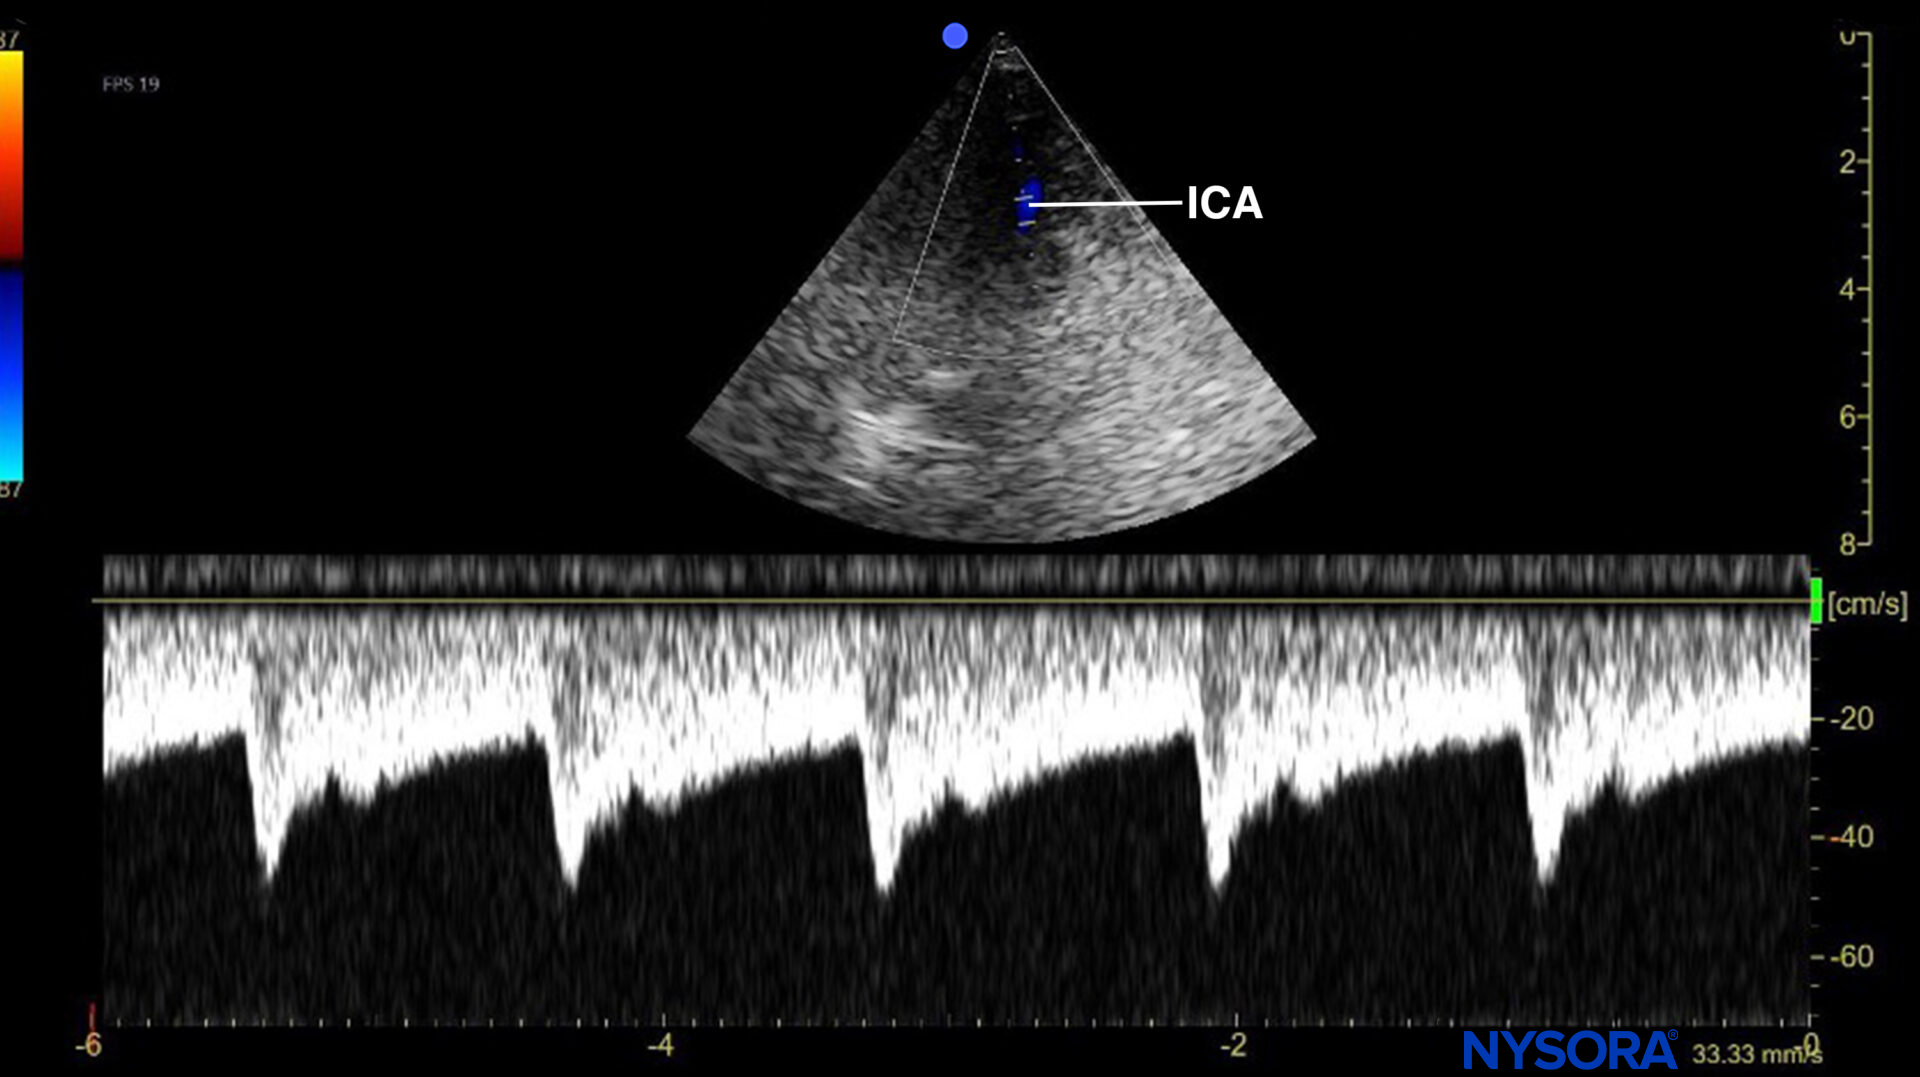

- Measure the flow velocities in the internal carotid artery (ICA).

Use the phased array transducer and position it high in the neck, pointing toward the vertex. Position the Doppler gate on the ICA to obtain the flow velocity, and trace it (usually 4-5 cm).

Pulsed wave Doppler of the flow in the (terminal extracranial) internal carotid artery (ICA). PSV, peak systolic velocity; EDV, end-diastolic velocity; MFV, mean flow velocity.